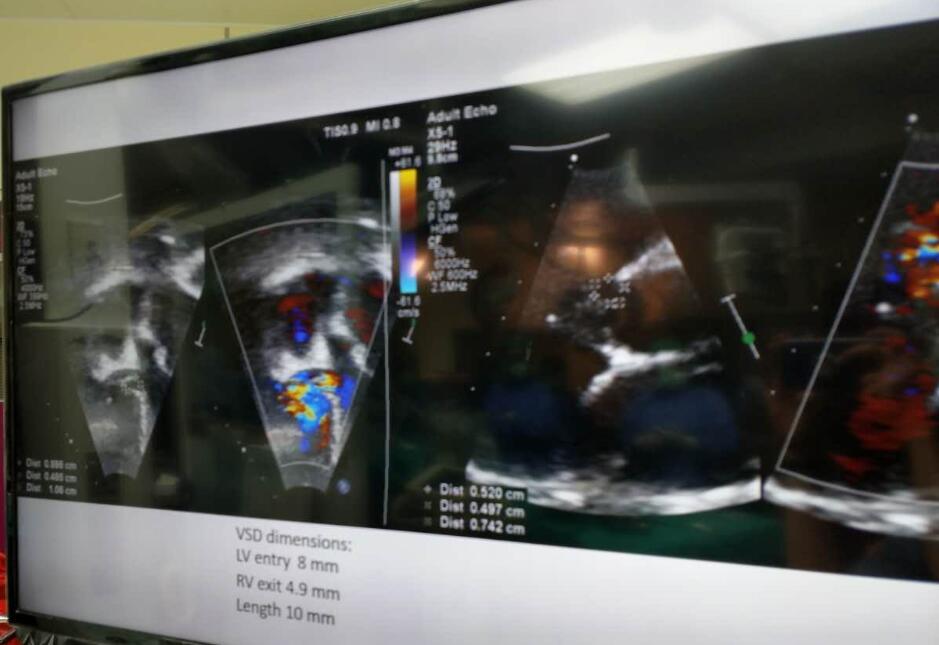

该患者被诊断为膜周部室距离缺损并伴有室缺瘤和三尖瓣反流,术中丈量患者瘤体左室入口为8mm,右室出口为4.9mm,瘤体长度为10mm,室缺通路较长。泰国Queen Sirikit医院的Dr.Worakan面对该复杂的情况,决定选用俄罗斯贵宾会集团科技公司型号为LT-MFO-6-4的KONAR-MF?多职能封堵器,通过动脉蹊径进行开释。KONAR-MF?多职能封堵器的腰部可能凭据病人室缺情况自适应调节,在对缺损部位齐全封堵的同时不合周边结构和神经造成影响,使得该例手术获得了极大的成功。

(术中超声)